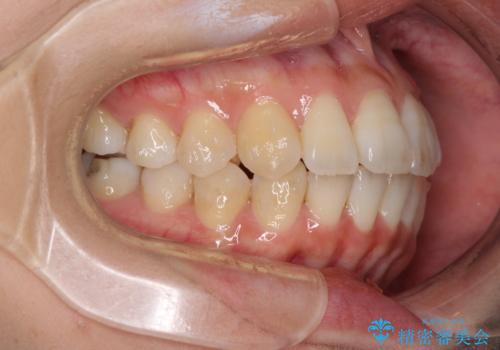

- 上下の歯の前後関係が乱れ、歯に負担がかかるとのことで来院された患者様です。

下顎が右左側に変位しているため、左側奥歯の咬み合わせが上下反対の関係となっていました。

また、上下ともに歯列が狭窄しており、奥歯以外にも反対咬合が認められました。